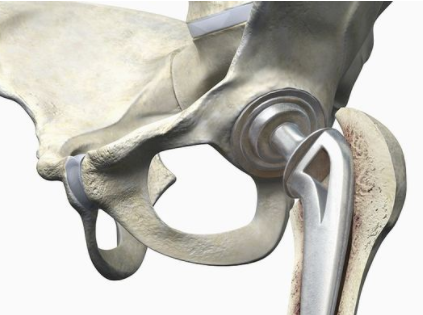

河南骨科专科医院:股骨头坏死关节置换的使用年限是

河南骨科专科医院介绍股骨头坏死是骨科比较常见的一种疾病,这种疾病发生以后,如果骨头已…[详情]